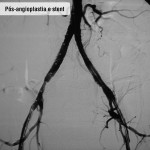

Tratamento endovascular

Pacientes com feridas necessitam de cirurgia na qual é feita punção na virilha, dilatação dos estreitamentos com balão e colocação de stent (molde metálico) para manter a artéria aberta. Com este procedimento, o paciente evita cortes, toma anestesia local e pode voltar para casa no mesmo dia (após seis horas de repouso) ou no dia seguinte. Para evitar novas lesões é imprescindível que a pessoa mude seus hábitos de vida, optando por um estilo mais saudável – inclui-se aí a prática regular de exercícios, a suspensão do fumo e o controle do colesterol e do diabetes.

Doença obstrutiva segmento aorto ilíaco – Caso 01

Doença obstrutiva segmento aorto ilíaco – Caso 02